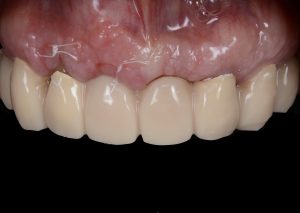

Healing abutments were removed and (b) the second set of temporary restorations was paced. Fig. 17 (i,ii)

Immediate post-operative view of the inserted provisionals. Fig. 19 (i,ii)